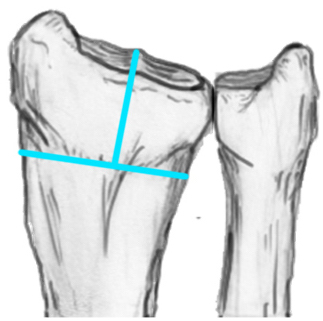

Distal Radius Angles

- radial volar tilt 11°

- radial inclination 22°

- radius is 11 mm longer than ulna

- ulna variance 2mm positive on average